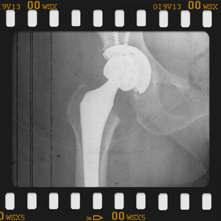

Peki kalça protezi ameliyatın da neler yapıyoruz? Diz protezi ameliyatındaki benzer aşamaları uyguluyoruz. Kalça eklemi dize göre yapısal olarak ve çalışma sistemi olarak farklıdır. Kalça eklemi bir yuva ve onun içinde hareket eden femur başı dediğimiz bir toptan oluşur. Kalça eklemi kireçlenmesinde bu baş ve yuva yüzeyindeki kıkırdakların aşınması sonucu başın yuvarlaklığı kaybolur, sonuçta ağrı ve hareket kısıtlılığı ortaya çıkar. Bu yüzeyleri değiştirirken öncelikle bu başı kesip atıyoruz. Daha sonra yuvayı yine kılavuzlarla oyup uygun büyüklükteki protezi sıkıştırdıktan sonra en az 2 vida ile kemiğe adapte ediyoruz. Daha sonra alt uyluk kemiğini yine kılavuzlar yardımı ile oyduktan sonra kemiğe adapte ediyoruz ve sistemi birleştiriyoruz.

Büyütmek için üzerine tıklayınız.